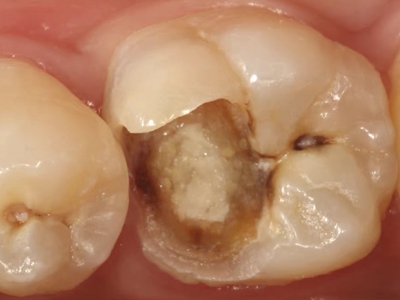

年轻恒牙龋指的是儿童萌出不久的第一恒磨牙龋病和上颌恒切牙龋病,其中第一恒磨牙龋病占年轻恒牙龋的90%,发病早,进展快,可表现为白垩色斑片、点隙窝沟墨浸状龋坏或龋洞。本病的发生和年轻恒牙的特点以及儿童饮食、口腔卫生等因素有关。

年轻恒牙龋好发于第一、二恒磨牙(牙合)面、邻面,上颌中切牙邻面,多为急性龋,龋坏进展快。平滑面的早期龋多为白垩色的斑片,点隙窝沟的早期龋多为浸墨状,表面粗糙。如果早期龋不及时治疗,可逐渐形成大而深的龋洞,易导致牙髓炎和根尖周炎。